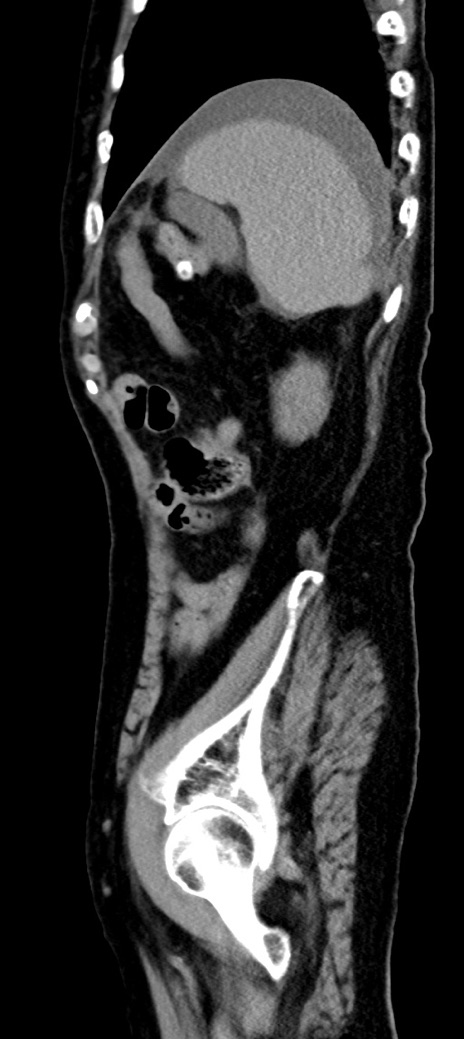

症例40(矢状断像)他院1日前

【症例】90歳代女性

【主訴】腹痛・嘔吐

【現病歴】 食欲低下、嘔吐があり昨日他院受診。肺炎と診断され入院となる。入院後より腹部全体に圧痛あり。胃管留置され経過みていたが、症状持続するため、

当院転院となる。

【既往歴】胸椎圧迫骨折、胆石症

【身体所見】腹部:中央に激痛あり、圧痛あり、反跳痛不明

【データ】WBC 17100、CRP 18.82

他院CT